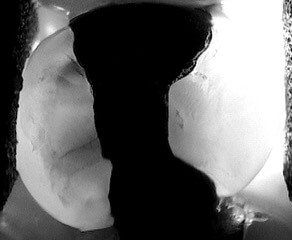

Ces photographies ont été prises avec l’utilisation de la technologie Lum G2. Elles permettent de démontrer son pouvoir dans le diagnostique des caries, des fractures et des fêlures.

Interprox - Clinique dentaire Morin-Houle in Hull